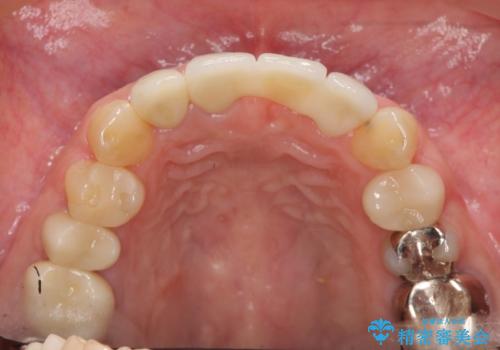

不良インプラントの除去・骨造成・歯肉移植・前歯審美セラミックブリッジ製作

不良インプラントを除去し最終的にブリッジによる補綴で審美性の改善を行うこと、その準備として骨の造成・歯肉の移植による歯の欠損部顎堤のボリュームを維持・増大を計画します。

- 65万円(仮歯・ファイバーコア・ジルコニアクラウン・インプラント除去・骨造成・歯肉移植)費用は治療当時の料金となります

より審美的な改善を強く求められたため、インプラントを除去し可及的に欠損部顎堤を増大したのちブリッジによる審美改善を行いました。